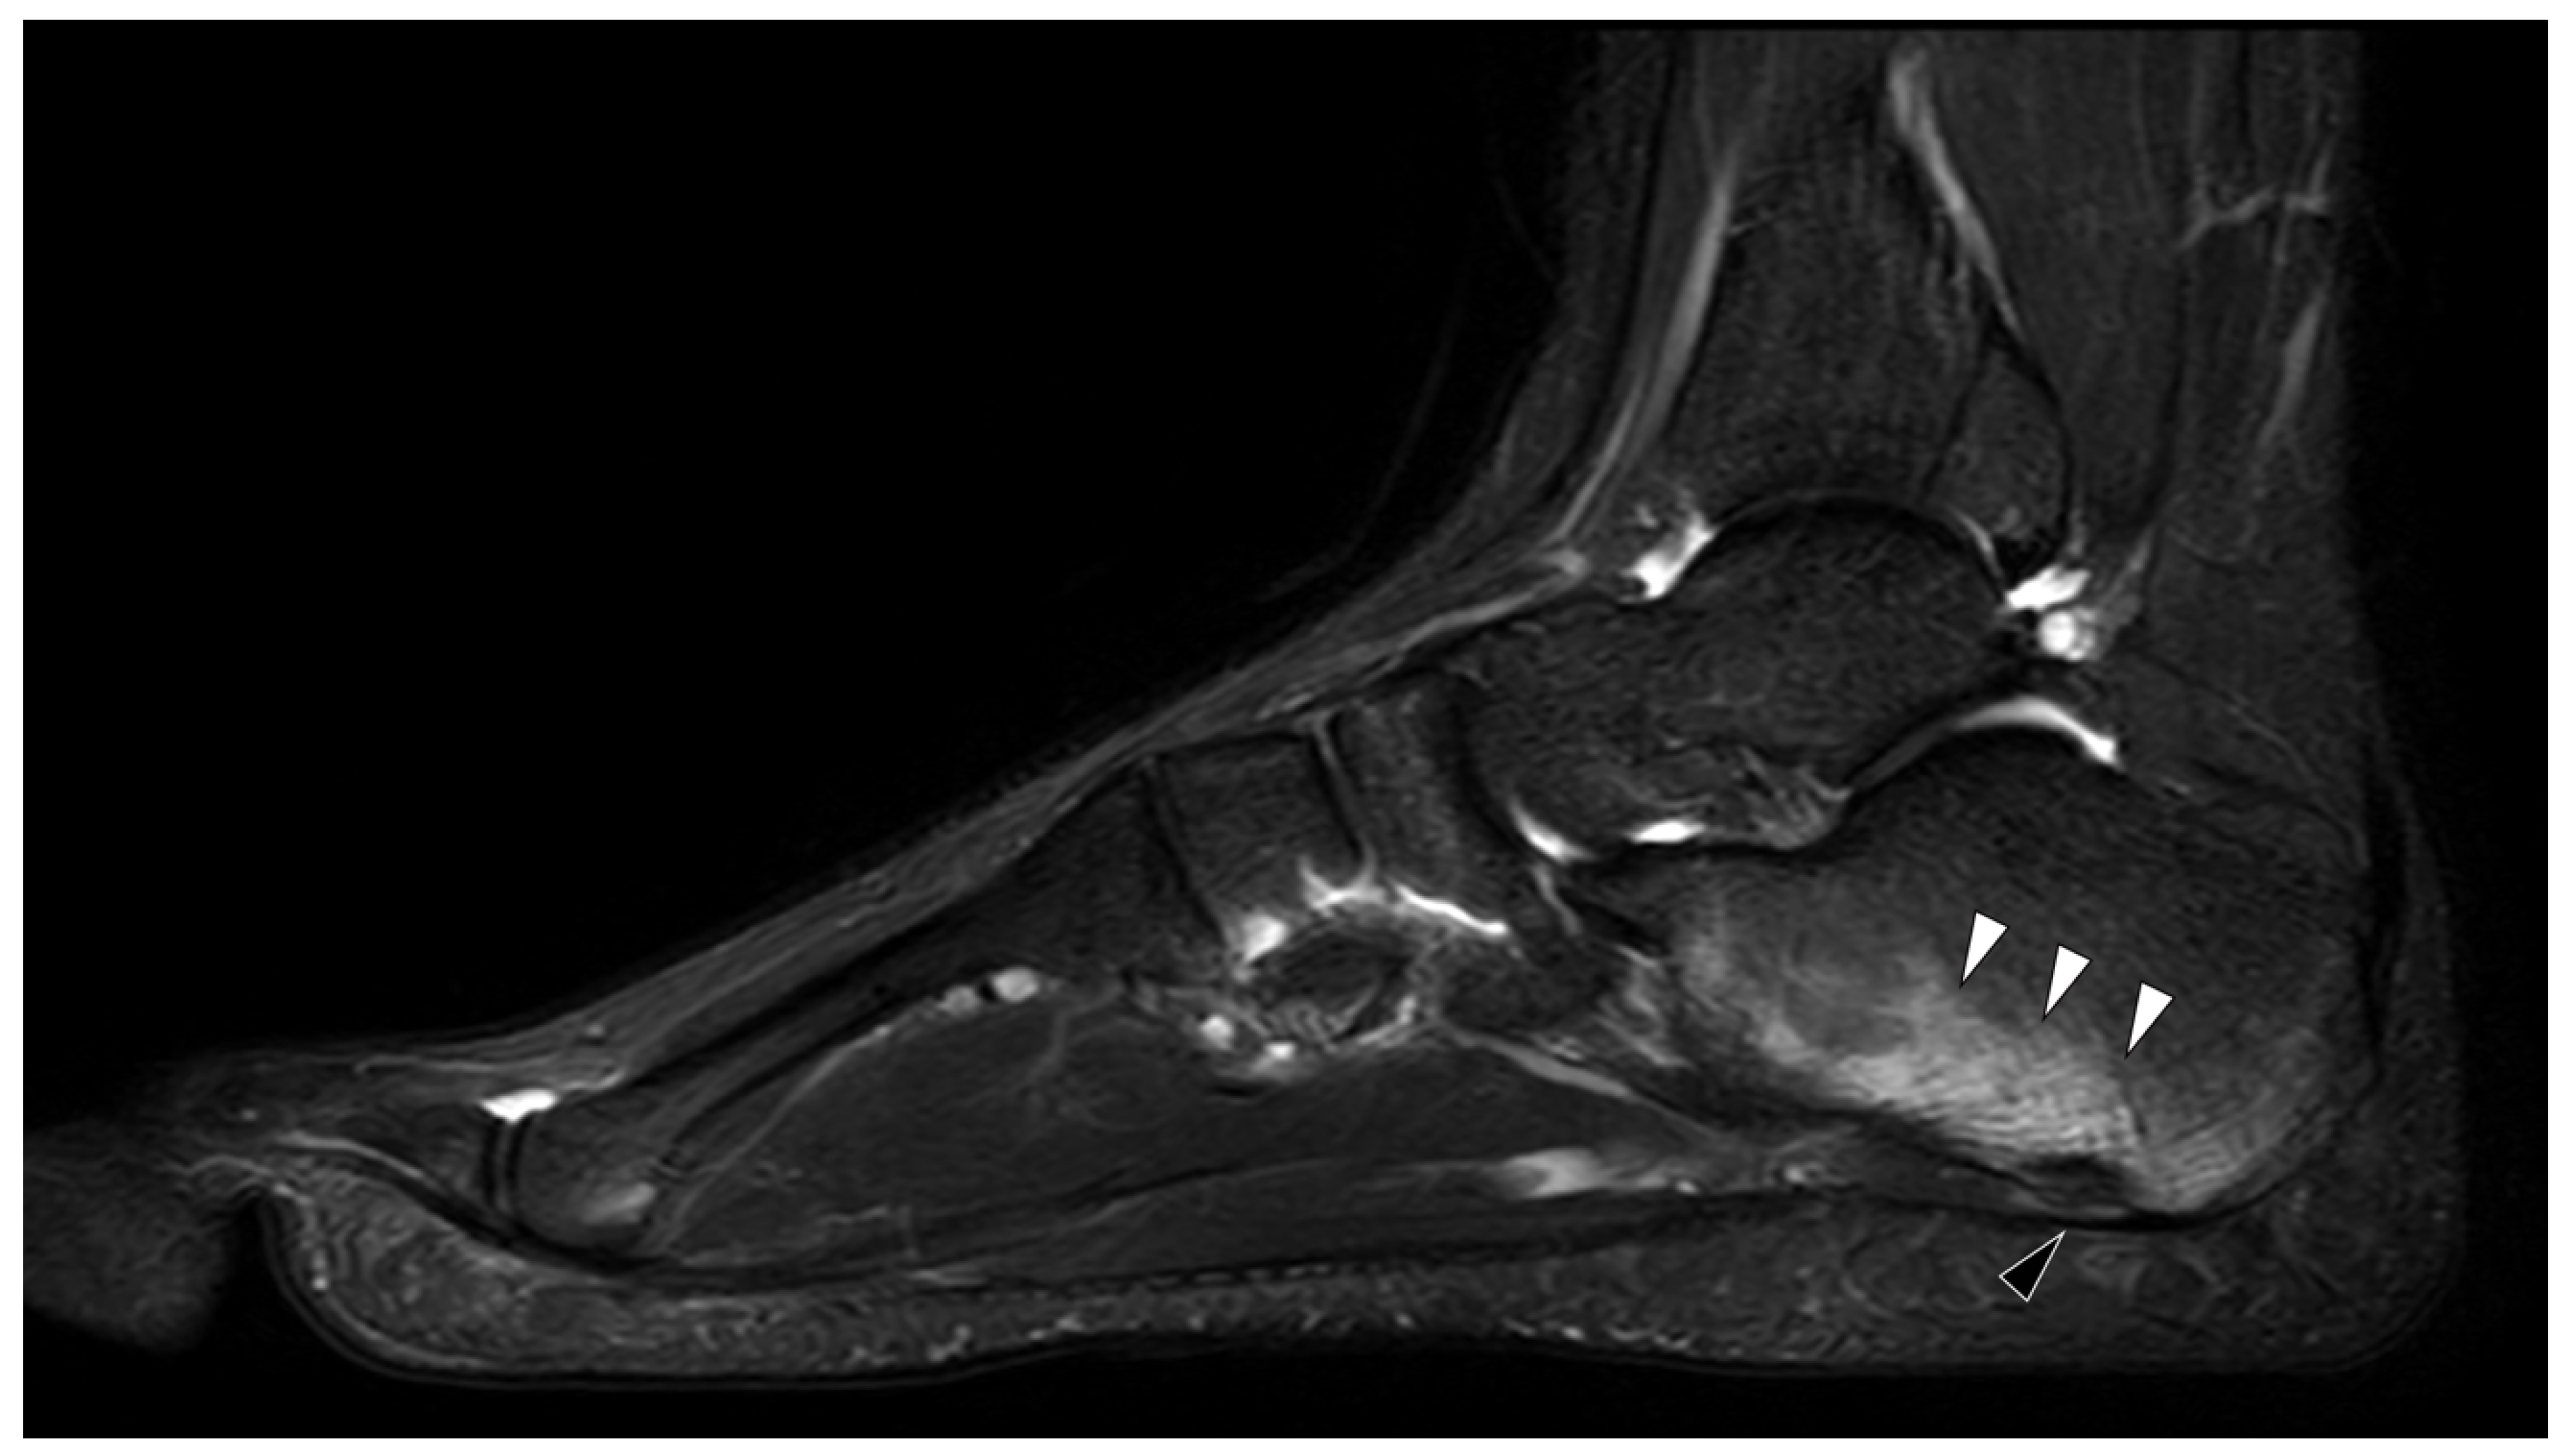

- Eshed, I.; Rosman, Y.; Livneh, A.; Kedem, R.; Langevitz, P.; Lidar, M.; Ben-Zvi, I. Exertional Leg Pain in Familial Mediterranean Fever: A Manifestation of an Underlying Enthesopathy and a Marker of More Severe Disease. Arthritis Rheumatol. 2014, 66, 3221–3226. [Google Scholar] [CrossRef]

- Eshed, I.; Bollow, M.; McGonagle, D.G.; Tan, A.L.; Althoff, C.; Asbach, P.; Hermann, K.-G. MRI of enthesitis of the appendicular skeleton in spondyloarthritis. Ann. Rheum. Dis. 2007, 66, 1553–1559. [Google Scholar] [CrossRef]

- Eshed, I.; Kushnir, T.; Livneh, A.; Langevitz, P.; Ben-Zvi, I.; Konen, E.; Lidar, M. Exertional leg pain as a manifestation of occult spondyloarthropathy in familial Mediterranean fever: An MRI evaluation. Scand. J. Rheumatol. 2012, 41, 482–486. [Google Scholar] [CrossRef]